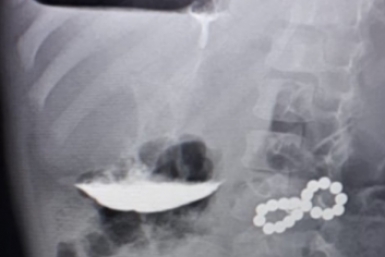

Какие методы контрацепции чаще используют жители Ставрополья, рассказал врач

Не все из них безопасны

Жители Ставрополья в качестве контрацептивов чаще используют барьерные методы и высокоаварийный прерванный половой акт. Последняя тенденция вызывает тревогу у врачей, рассказал в интервью корр. ИА Stavropol.Media заместитель главврача по акушерско-гинекологической помощи Ставропольского краевого клинического перинатального центра Владислав Зубенко.

Как отметил врач, ситуация повторяет общероссийскую статистику. Оральные контрацептивы тоже популярны, но нередко их принимают без должного обследования. А вот современные варианты, такие как гормональные импланты или системы, известны гораздо меньше. Ситуацию может исправить новый документ с описанными стандартами методов контрацепции, считает врач. Клинические рекомендации впервые разработали в России — до этого медикам пришлось опираться на международный и личный опыт.

"Новые рекомендации — это инструмент, чтобы исправить этот дисбаланс через просвещение", — поделился заместитель главврача.